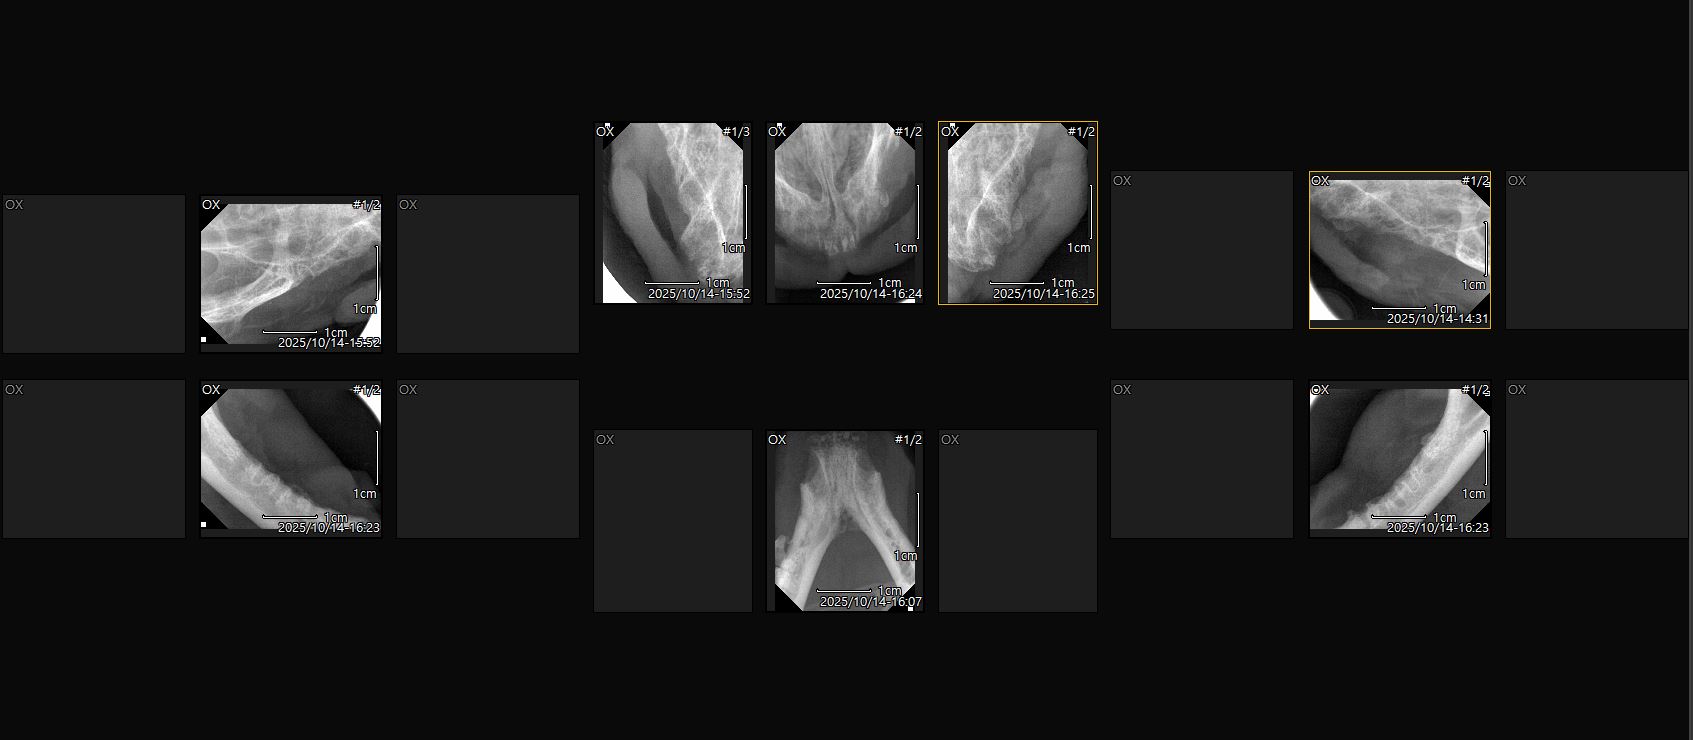

| 치료전 대상묘 사진 |      |

| 치료과정 | 14일 치과치료 예약을 잡고 13일 퇴근하고 아이를 포획하러 갔습니다 그날은 가을비가 내리던 날이었어요 비가 와서 오늘은 포획을 포기할까도 싶었지만 그렇게 되면 병원예약에 맞춰서 다시 예약을 해야하는데 이러다간 구조가 늦어질것같아서 일단 시도를 했습니다 포획틀을 설치하고 방수커버를 씌운뒤 멀찌기 떨어져서 기다렸습니다 빗줄기가 거셀땐 차밑에서 나오질 않았고 주춤해지면 나와서 주변만 맴돌았어요 비는 오고 시간은 흐르고 날은 어두워지고 제 마음은 정말 타들어가게 조바심이 났습니다 이대로 실패하나 철수할까.. 그래도 조금만 더 기다려보자 하여 1시간을 넘게 서로 비에 젖어가며 대치하다 겨우 구조에 성공, 바로 동물병원으로 데려가서 입원을 시키고 다음날 원장님께서 출근하셔서 수술에 필요한 검사를 하시고 건강상 큰 이상이 없다 판단하여 바로 전발치 수술과 중성화 수술을 같이 했습니다 pcr결과 칼리시가 발견되었고 칼리시에 의한 구내염으로 진단을 내리셨고 목구멍에도 염증이 많아서 며칠 수액을 맞았습니다 칼리시로 인한 구내염이라 완치가 될진 지켜보는수밖에 없다 하셨어요 수술하고 난 뒤 상태는 어떤지 검사를 해야하는데 아이가 생각보다 경계심이 많아서 어쩔수없이 살짝 재우고 검사 및 인터페론 주사처치를 했고 그 후로는 경계심도 조금씩 줄어들고 크게 아파하거나 불편해하지 않고 밥도 잘 먹는다해서 수액은 제거하고 입원만 진행했습니다 저희집에서는 케어를 해줄수없어 병원에 2주 조금안되게 입원하면서 중간중간 체크도 해주시고 컨디션이 어느정도 좋아졌을땐 예방접종도 한차례 진행했습니다 넥카라 때문인지 목구멍 염증 때문인지 수술하고 얼마 지나지 않아서인지 여전히 입가에 조금씩 침이 맺혀있긴 했어요 병원에서도 봐주시긴 했지만 중간중간 제가 가서 먹을거 먹는 모습도 보면서 원장님과 상의후 퇴원 날짜를 정했습니다 |

| 대상묘 치료중 사진 |      |